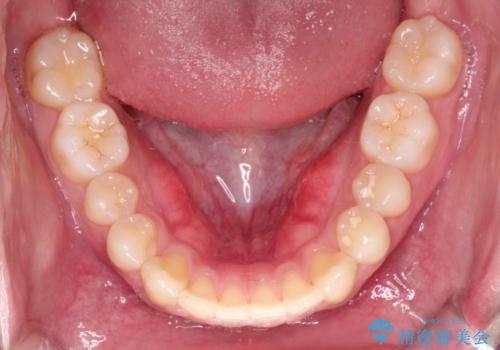

【クリア装置】前歯の凸凹を綺麗にしたい

- 前歯の凸凹を主訴に来院されました。

マウスピース矯正も適応でしたが、ワイヤー矯正を希望され治療を行なっております

治療期間も短く大変満足していただきました。